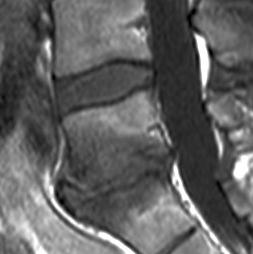

Discopathies L4-L5 et L5-S1 MODIC 1